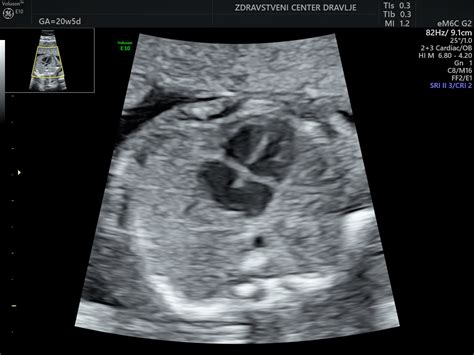

Anjina zgodba se je začela na rutinski morfologiji v 20. tednu nosečnosti, ko je ginekologinja zaznala nepravilnosti pri srčku ploda. Sledili so pregledi v porodnišnici Ljubljana in na pediatrični kliniki, kjer so potrdili diagnozo: hud hipoplastični levi ventrikel. Po posvetu s strokovnjaki je postalo jasno, da operacija po porodu ne bo mogoča in da bi otrok lahko preživel le nekaj ur, s kakršnokoli posegom le podaljšali njegovo trpljenje. Ta spoznanja so vodila v težko odločitev o prekinitvi nosečnosti.